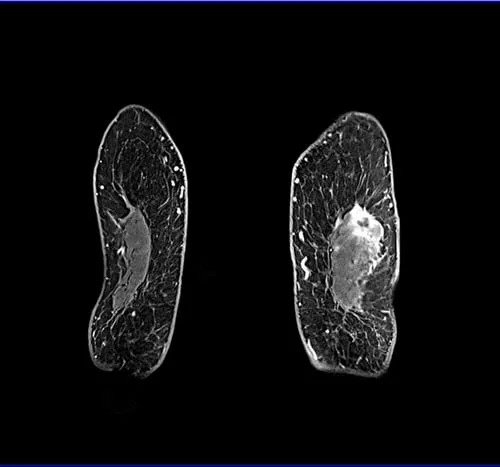

VIBE FAT SAT Coronal POST CONTRAST SEQUENCE USED IN BREAST IMAGING